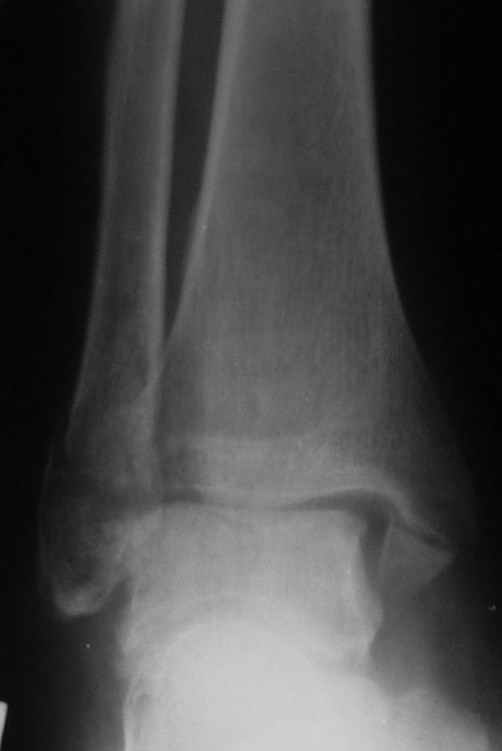

Ниже рентгенограммы

До операции 28 июля